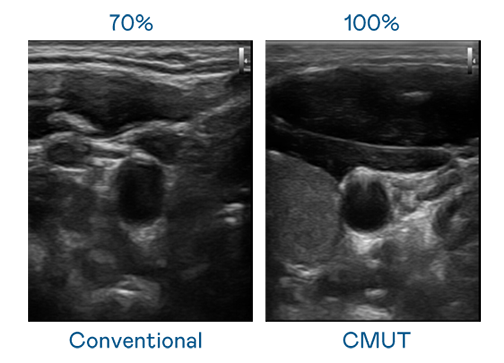

CMUT 技术是一种用电容式微机电元件来产生超音波讯号的技术。与传统 PZT 压电式技术相比,CMUT 频宽增加 30%,更宽频的超音波讯号让影像解析度大幅提升,是实现高影像品质医疗超音波扫描、促进精准医疗发展的关键技术。

超音波影像的解析度高低,首先取决于探头能发出的讯号频宽。圣淘沙 CMUT 可提供高清晰的超音波讯号,提供高频宽、高灵敏度、影像纹理细节更高的超音波影像,协助医护人员缩短影像判读时间及利用精准的医疗影像进行诊断。